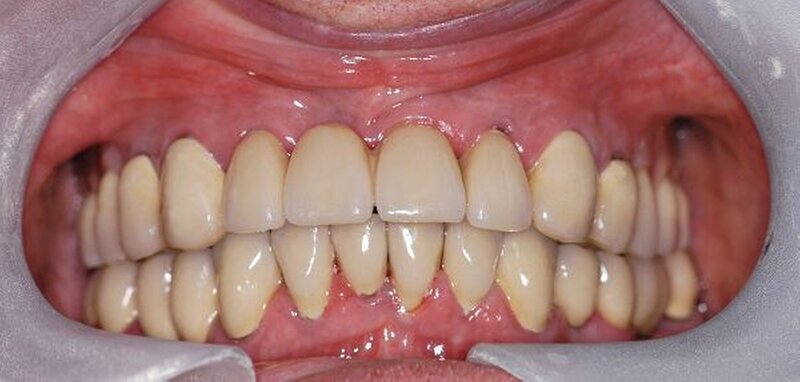

In der darauf folgenden Sitzung wurden alle Kronen und Brücken sowie die teleskopgetragene, partielle obere Prothese für einen Zeitraum von sieben Tagen zum Probetragen mittels eines Zements auf Zinkoxid-Eugenol-Basis eingegliedert. Dem Patienten sollte durch das Probetragen der Restaurationen beziehungsweise des angefertigten Zahnersatzes die Möglichkeit gegeben werden, sowohl die Funktion beim Essen und Sprechen als auch die Ästhetik im sozialen Umfeld zu testen. Ein erneutes Entnehmen der Restaurationen wäre – für den Fall notwendiger Korrekturen – somit ohne Weiteres möglich gewesen. Da der Patient sowohl die Funktion als auch die Ästhetik betreffend keine Änderungswünsche vorbrachte und auch keine neuerlichen Beschwerden aufgetreten waren, konnten die Restaurationen nach besagtem Tragezeitraum von sieben Tagen entnommen, gesäubert und mittels eines Glasionomerzements definitiv befestigt werden. Im Anschluss wurden erneut Situationsabformungen der Kiefer genommen und der Patient erhielt nach erneutem Checkbiss-Registrat, eine okklusal adjustierte Stabilisierungsschiene im Unterkiefer. Diese dient der Therapie der beschriebenen Bruxismusproblematik und gewährleistet einen langfristen Erfolg der eingegliederten prothetischen Restaurationen (Abbildungen 13a, 13b, 13c, 14, 15a, 15b, 15c).

Abschließend kann somit festgehalten werden, dass durch die gewählte Restaurationsform sowie durch die Art der technischen Umsetzung ein funktionell und ästhetisch sehr gutes Ergebnis erreicht werden konnte. Die Prognose des angefertigten Zahnersatzes ist bei entsprechender Compliance des Patienten sowie aufgrund der guten werkstofftechnischen Eigenschaften über einen Zeitraum von vielen Jahren als sehr gut einzustufen (Abbildungen 16a, 16b, 16c, 16d, 16e ).